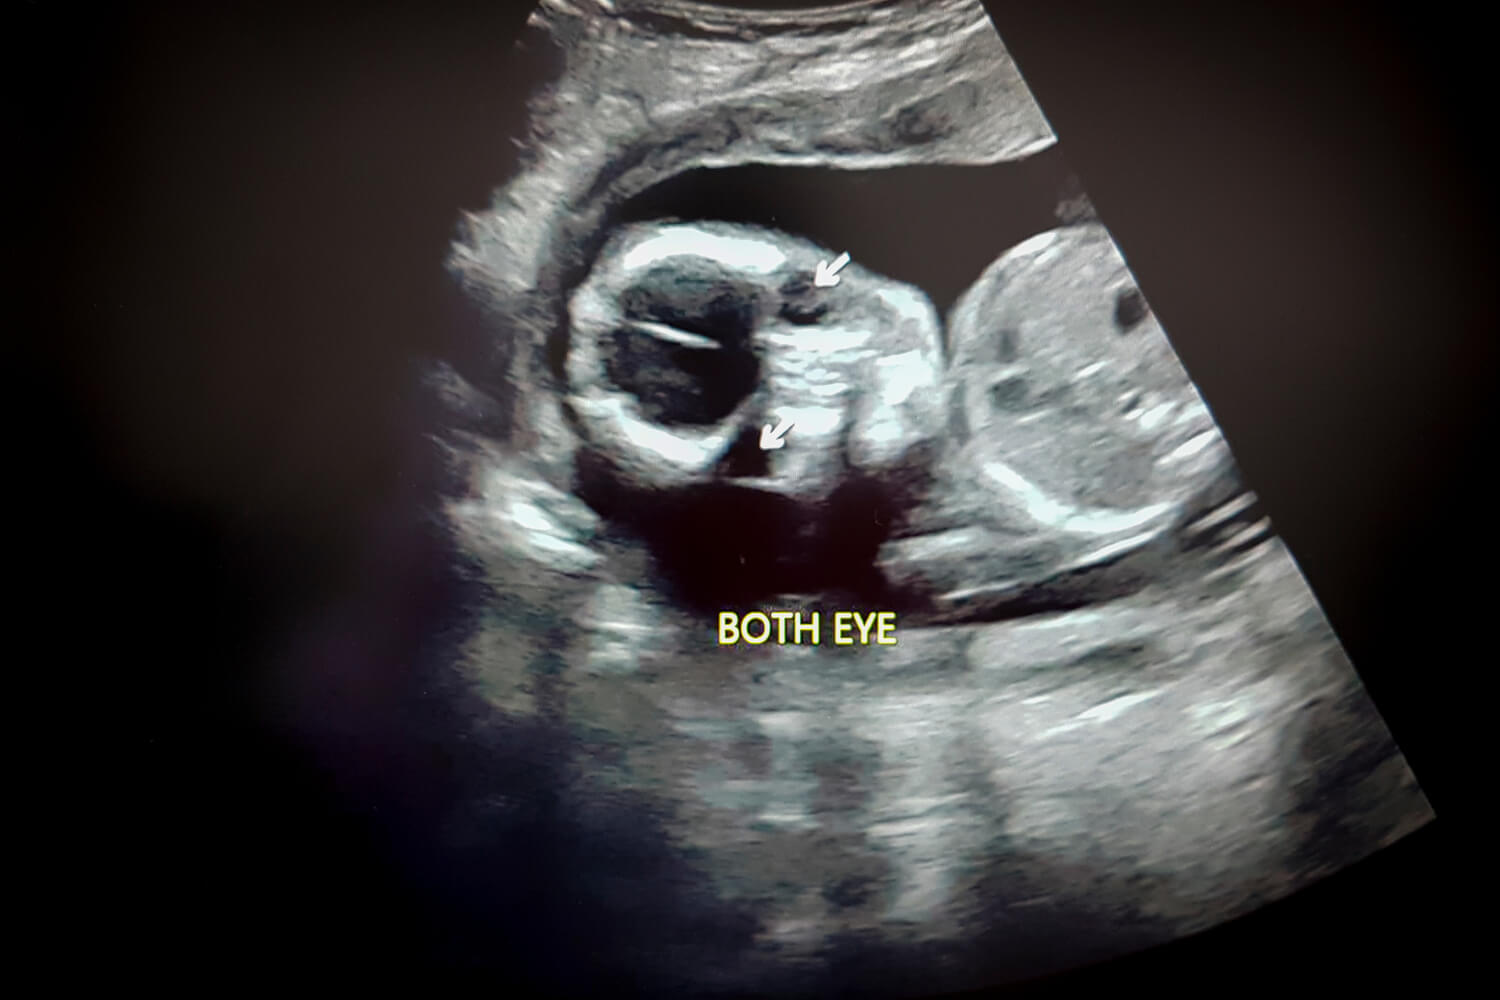

Babies’ eyes develop well enough during pregnancy. They can understand shapes, certain colours, and light. Though they take time to adjust to the light around them after birth, they are born with eyes and sight.

The iris, pupil, lens, cornea and retina start developing in both eyes, around the seventh week of pregnancy.